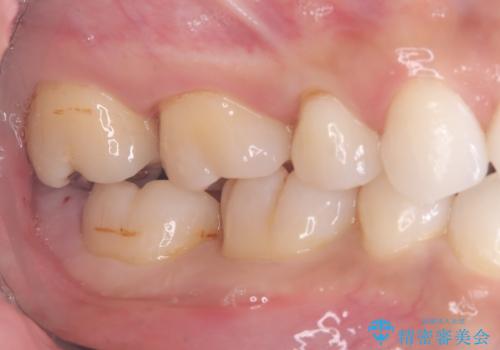

来院時、右下7遠心9mm、舌側6mmと深い歯周ポケットを認めました。

遠心から舌側、唇側に及ぶ深い垂直的骨欠損も認めたため、歯科衛生士による歯周基本治療の後、歯周外科(再生療法)を行いました。

レントゲン写真は、処置後一年経過時のもので、歯周ポケットは遠心4mm、舌側3mmまで減少、出血なし。